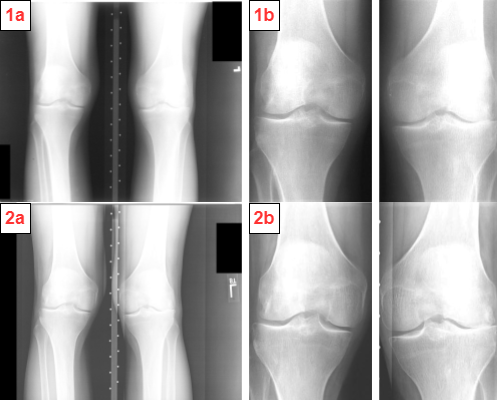

Refer to caption

Figure 9: Preprocessed knee radiographs (1b, 2b) generated after joint localization [37] and global contrast normalization [58] on original samples (1a, 2a)